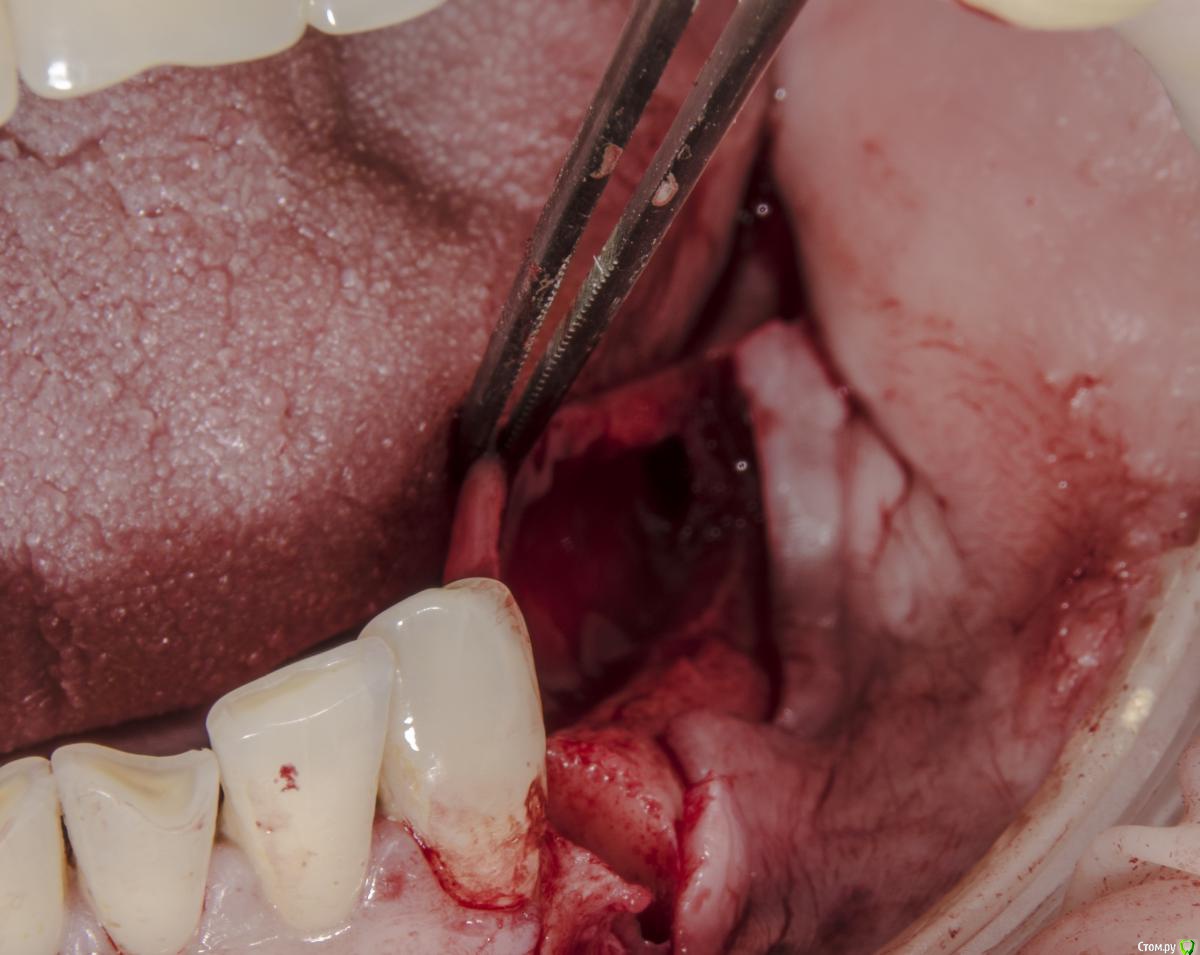

kamranchick Опубликовано 3 мая, 2016 Автор Поделиться Опубликовано 3 мая, 2016 Тут 2ух этапно я пошёл, сначала НКР Ссылка на комментарий

kamranchick Опубликовано 27 мая, 2016 Автор Поделиться Опубликовано 27 мая, 2016 Сори за качество фото... 1 Ссылка на комментарий